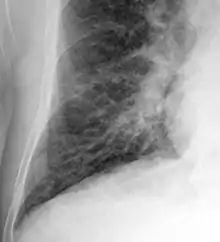

Kerley B lines in radiograph of acute cardiac decompensation. The short, horizontal lines can be found everywhere in the right lung.

Chronic stable heart failure may easily decompensate. This most commonly results from a concurrent illness (such as myocardial infarction (a heart attack) or pneumonia), abnormal heart rhythms, uncontrolled hypertension, or a person's failure to maintain a fluid restriction, diet, or medication.[51]